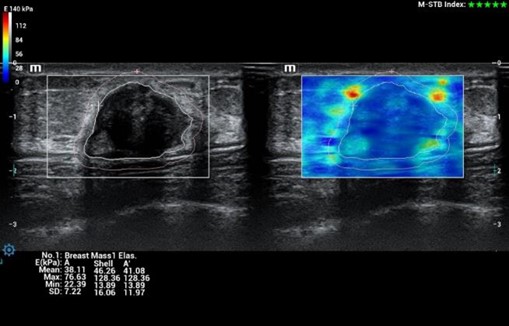

- STE - Shear wave elastografia pre presnejšiu kvantifikáciu tuhosti tkaniva,

- STRAIN ELASTOGRAFIA (Natural Touch)

STE - Sound Touch Elastografia, 2D shear wave elastografia v reálnom čase

Strain Elastography - Natural Touch Elastografia

HiFR STE (Shear wave elastografia🙂 ZST+ UZV platforma umožňuje 10 krát rýchlejší STE frame rate ako u štandardných UZV prístrojov pri zachovaní hladkosti a konzistentnosti obrazu. Senzitívnejšia detekcia pohybu, lepšia stabilita vyššia presnosť. Unikátny M-STB index indikujúci pohybovú stabilitu obrazu. Presná kvantifikácia tuhosti pečene pomáhajúca pri gradingu a prognóze fibrózy a cirhózy pečene

HiFR STE Elastography: Kompletná a výkonná elastografia. Shear Wave Elastografia (HiFR STE, STQ). Strain - Natural Touch Elastografia (NTE). Vysoká citlivosť, penetrácia a presnosť. Unikátna “shell” analýza hodnotiaca infiltráciu tumoru do okolia. Automatické ohraničenie ložiska a shear wave kvantifikácia tuhosti tkaniva. Presné posúdenie tuhosti tkaniva pomôže v diagnostickom odlíšení malígneho a benígneho nálezu.

HiFR STE Elastography: Kompletná a výkonná elastografia. Shear Wave Elastografia (HiFR STE, STQ). Strain - Natural Touch Elastografia (NTE). Vysoká citlivosť, penetrácia a presnosť. Unikátna “shell” analýza hodnotiaca infiltráciu tumoru do okolia. Automatické ohraničenie ložiska a shear wave kvantifikácia tuhosti tkaniva. Presné posúdenie tuhosti tkaniva pomôže v diagnostickom odlíšení malígneho a benígneho nálezu.